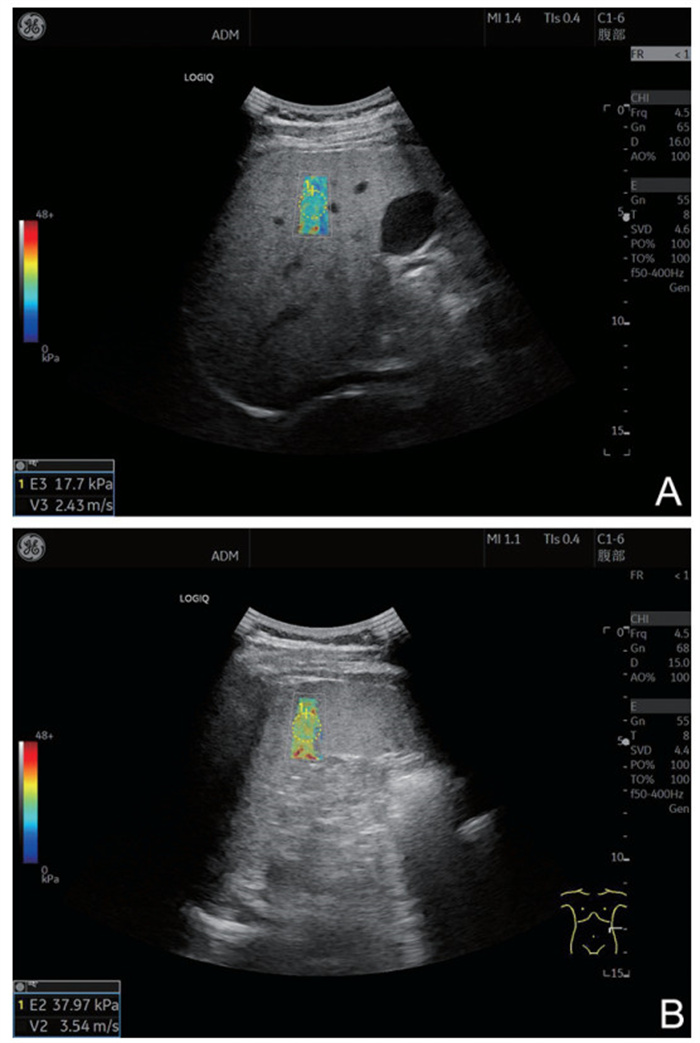

目的  肝硬化食管胃静脉曲张(EGV)再出血的病理生理机制复杂,且病死率高,明确其再出血的危险因素对降低病死率有重要作用。二维剪切波弹性成像(2D-SWE)能无创、定量地评估肝脏软硬程度,反映肝脏的病理改变。本研究基于2D-SWE构建EGV再出血风险模型,为临床防治提供参考。  方法  选取2020年1月—2022年12月郑州大学附属郑州中心医院收治的162例肝硬化EGV首次出血患者,根据患者是否发生再出血将其分为未再出血组(127例)和再出血组(35例)。采用logistic回归分析研究肝硬化患者EGV再出血的危险因素。构建肝硬化患者EGV再出血的列线图预测模型,并评估列线图模型预测效能。  结果  未再出血组肝功能Child-pugh分级A级、食管胃静脉曲张程度轻度、ALB水平较再出血组更高,未再出血组首次套扎、肝硬度、脾硬度较再出血组更低(P<0.05)。Logistic多因素回归分析结果显示,肝功能Child-pugh分级、肝硬度、脾硬度、ALB均是肝硬化发生EGV再出血的独立影响因素(P<0.05)。ROC曲线分析结果显示,列线图模型C-index指数为0.903(95% CI:0.846~0.975),列线图模型实测值与预测值基本一致,预测价值较高,具有较好的临床有效性。  结论  2D-SWE检测肝脾硬度是影响EGV再出血的危险因素,基于此构建的列线图预测模型对EGV再出血具有较好的预测效能。